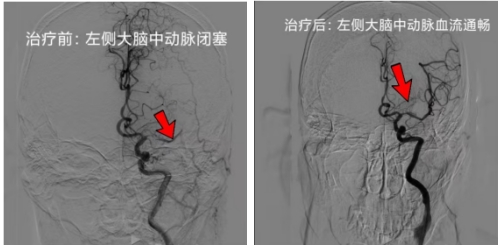

神经内科副主任严明敏接到呼叫后第一时间到达急诊,安排患者进入卒中绿色通道。此时患者意识、语言不清,双眼向左侧凝视,右侧肢体肌力2级,CTA检查发现左侧大脑中动脉闭塞。

另一边,神经内科副主任彭涛、介入组长杨昊为患者行左侧大脑中动脉取栓术及球囊扩张成形术,后复查显示大脑中动脉血流恢复通畅。